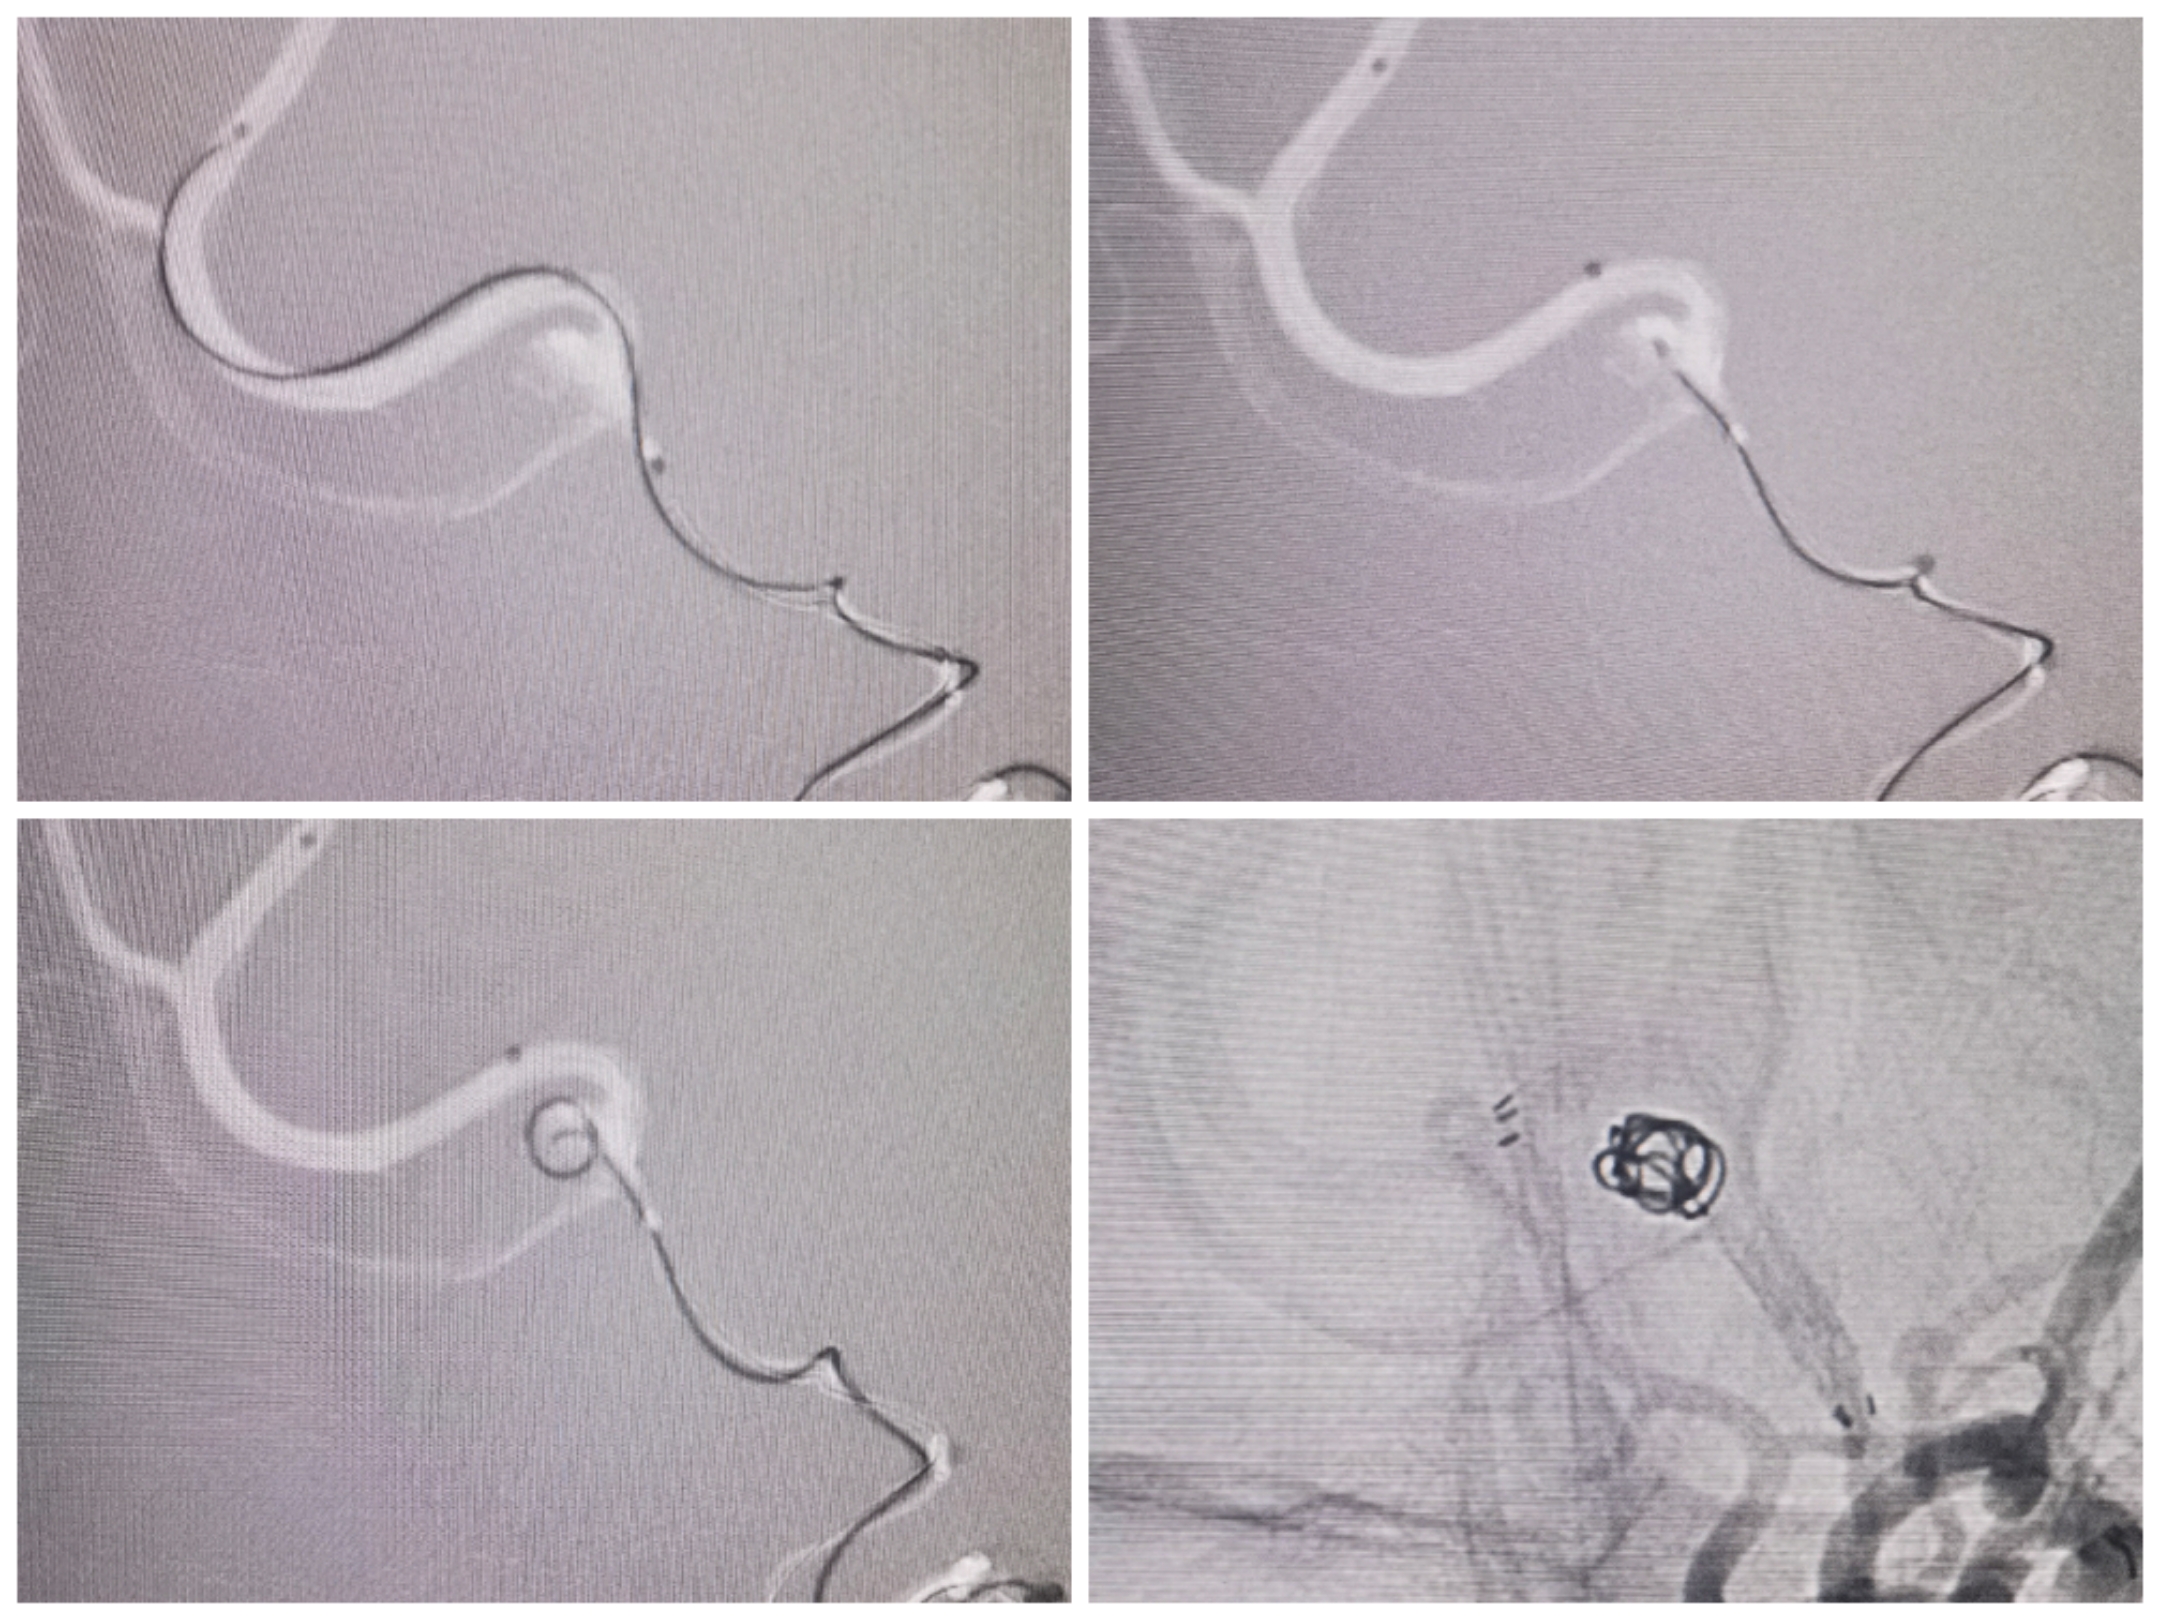

栓塞过程:塑了S型指向微管。

术后情况:前交通动脉瘤栓塞术后。双侧大脑前动脉显影良好

微导管塑形情况。

支架导管、微管到位情况

术后栓塞情况:支架开放良好,弹簧圈致密栓塞,双侧大脑前血流良好